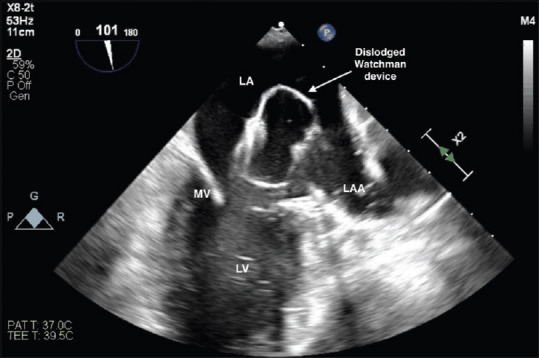

Abstract: WATCHMAN (Boston Scientific, Plymouth, MN, USA) is the most commonly utilized left atrial appendage occlusion device. Although increased operator experience has led to a significant decline in reported complications, serious and potentially fatal events can still occur. We present a case of WATCHMAN device embolization that was identified using transesophageal echocardiography shortly after device deployment, along with the subsequent management and retrieval of the device.